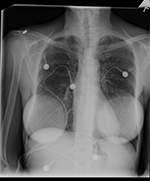

| 50 year-old woman with chest pain required evaluation of pulmonary embolism. Tc 99m MAA (macro aggregated albumin) scan (A) demonstrated well-defined rounded area of photopenia seen on anterior and left and right anterior oblique views due to photon attenuation from breast prostheses as seen on PA chest radiograph (B). |